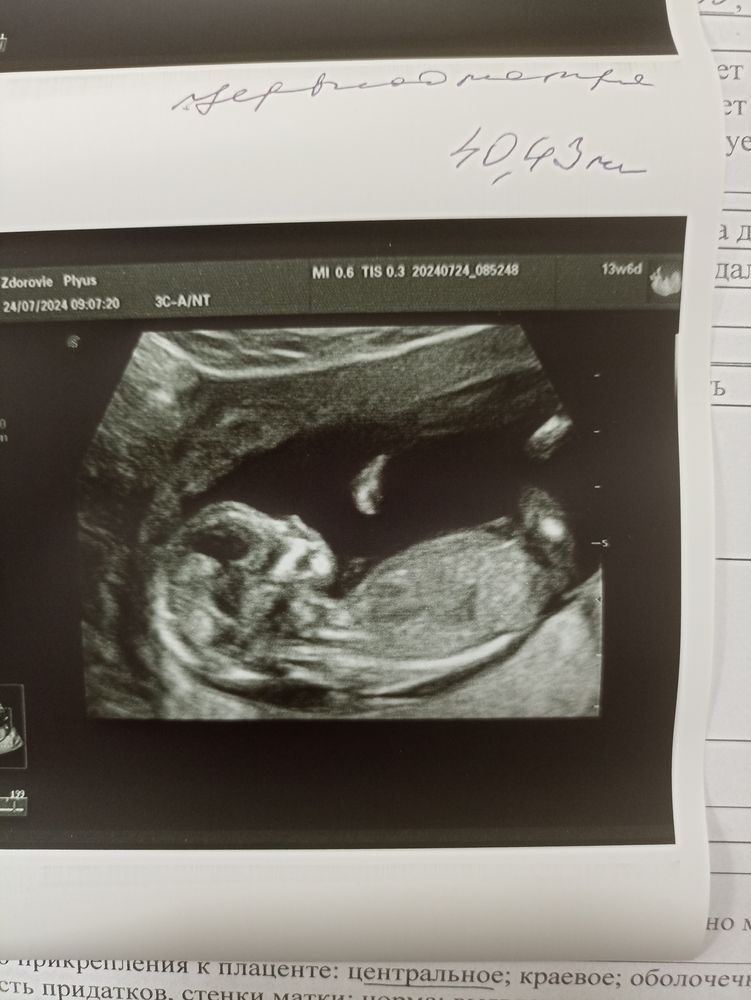

Katiii в Благополучная беременность год Как вам кажется девочка или мальчик? Анализы, скрининги Первый сынок ,очень хочется девчонку 😇 Посмотрите еще 20 записей на эту тему Лучший ответ Ника Девочка 🌸 25.07.2024 Ответить Отменить Ответить Дарья Девочка 25.07.2024 Ответить Katiii Как вы это видите ?₽) 25.07.2024 Ответить Леди баг Katiii, половой бугорок торчит прямо) так что, с большОй вероятностью, девочка. Был бы он задран вверх, то это говорит о мальчике. 25.07.2024 Ответить Елена Паршина Леди баг, а у нас как думаете? Или не понятно 25.07.2024 Ответить Леди баг Елена Паршина, не видать положение бугорка, как раз ножка закрыла, так что 50/50😄 25.07.2024 Ответить Замена клион д! Повышенный риск по Т21 РБ Чаты Беременных Выберите чат: Январята-2026 Февралята-2026 Мартята-2026 Апрелята-2026 Майчата-2026 Июнята-2026 Июлята-2026 Августята-2026